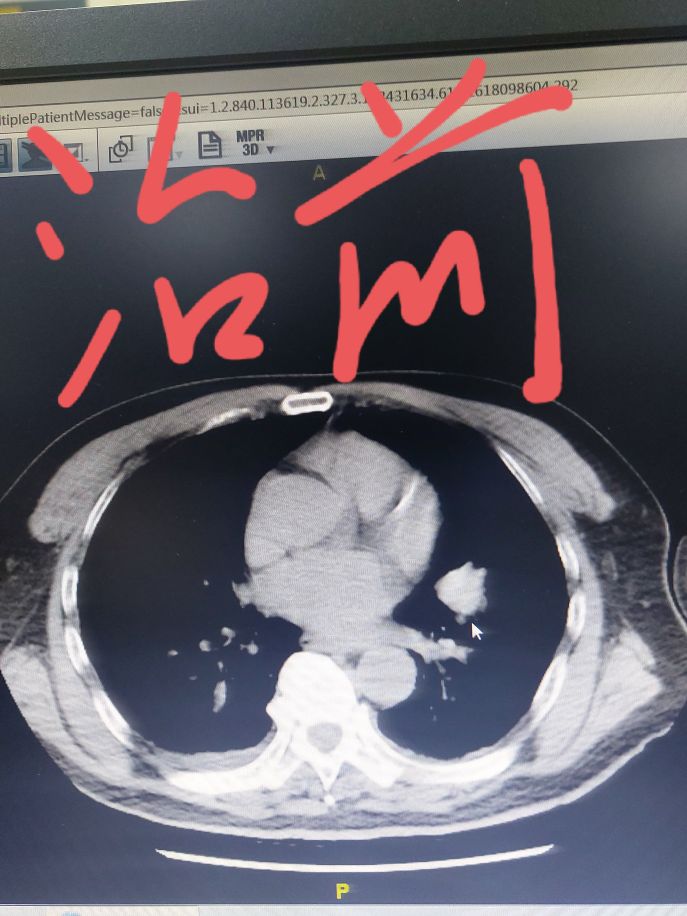

我给大家看一个具体的病例,这位患者几个月之前在我这里住院,当时左上肺有一个肿瘤,同时肺门纵隔淋巴结比较大,要说手术也不是不行,关键这位患者心脏还不好。这样的分期直接手术效果不太确定,所以我给他设计了先做两个周期药物治疗,然后再手术的策略。大家可以看一下下面的截图,通过穿刺这个患者病理是一个倾向于肺鳞癌,我给用的化疗加免疫药物的方案,进行了两个周期治疗,从我发的照片可以看到,做了两个周期治疗之后,肿瘤明显就减小了。